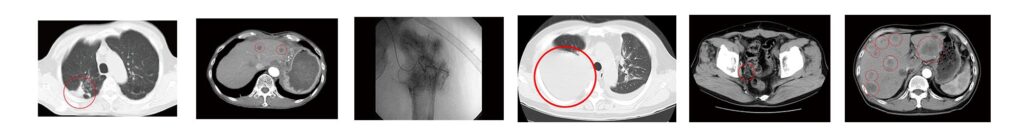

17) 大腸がん症例①②③

抗がん剤治療/放射線治療/外科手術と

併用治療 が可能です

かかりつけ病院で化学療法や放射線治療の標準治療を行いながら、MHCクラス1ネオアンチゲン複合免疫治療の併用が可能です。